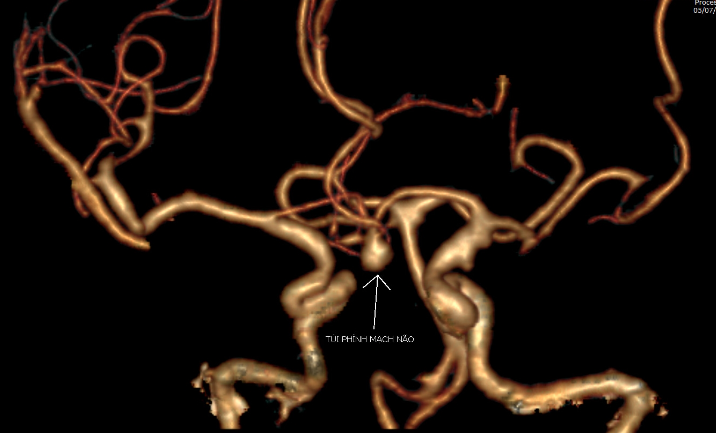

Kết quả chụp cắt lớp vi tính tại Bệnh viện Đa khoa tỉnh Quảng Ninh hôm 5/7 phát hiện ông T. chảy máu khoang dưới nhện do vỡ phình động mạch não thông trước, kích thước túi phình 5x6mm.

Thầy thuốc quyết định can thiệp nút mạch cầm máu khối phình bị vỡ nhằm ổn định tình trạng xuất huyết và tránh nguy cơ tái xuất huyết cho người bệnh. Kỹ thuật được sử dụng là nút coil. Theo đó, phẫu thuật viên luồn vi ống thông từ động mạch đùi lên đoạn mạch não bị tổn thương, tiếp cận túi phình động mạch não thông trước và thực hiện nút bít túi phình bằng vòng xoắn kim loại (Coil) dưới hệ thống chụp mạch số hóa xóa nền 2 bình diện (DSA).

Kết quả chụp mạch kiểm tra thấy, túi phình bị vỡ đã được bít hoàn toàn, tuần hoàn động mạch não hồi phục trở lại.